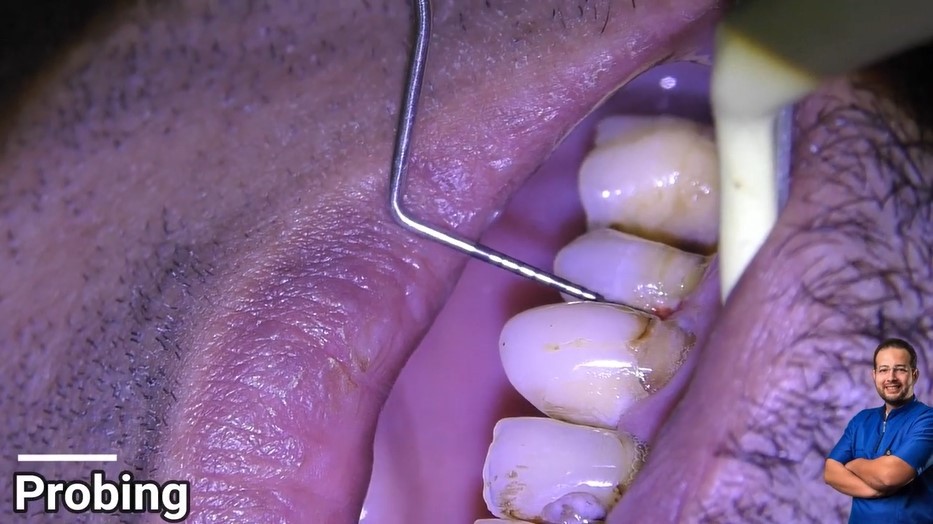

Treatment case sharing from dr wael